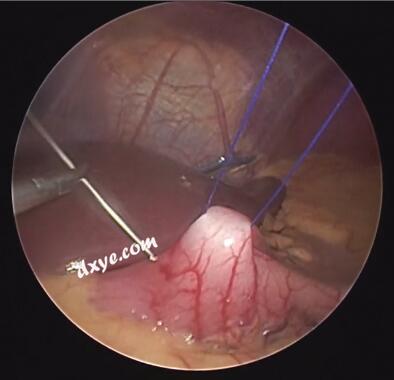

1:23 再吊一针,重复一次

5.jpg

3:07 单手转针